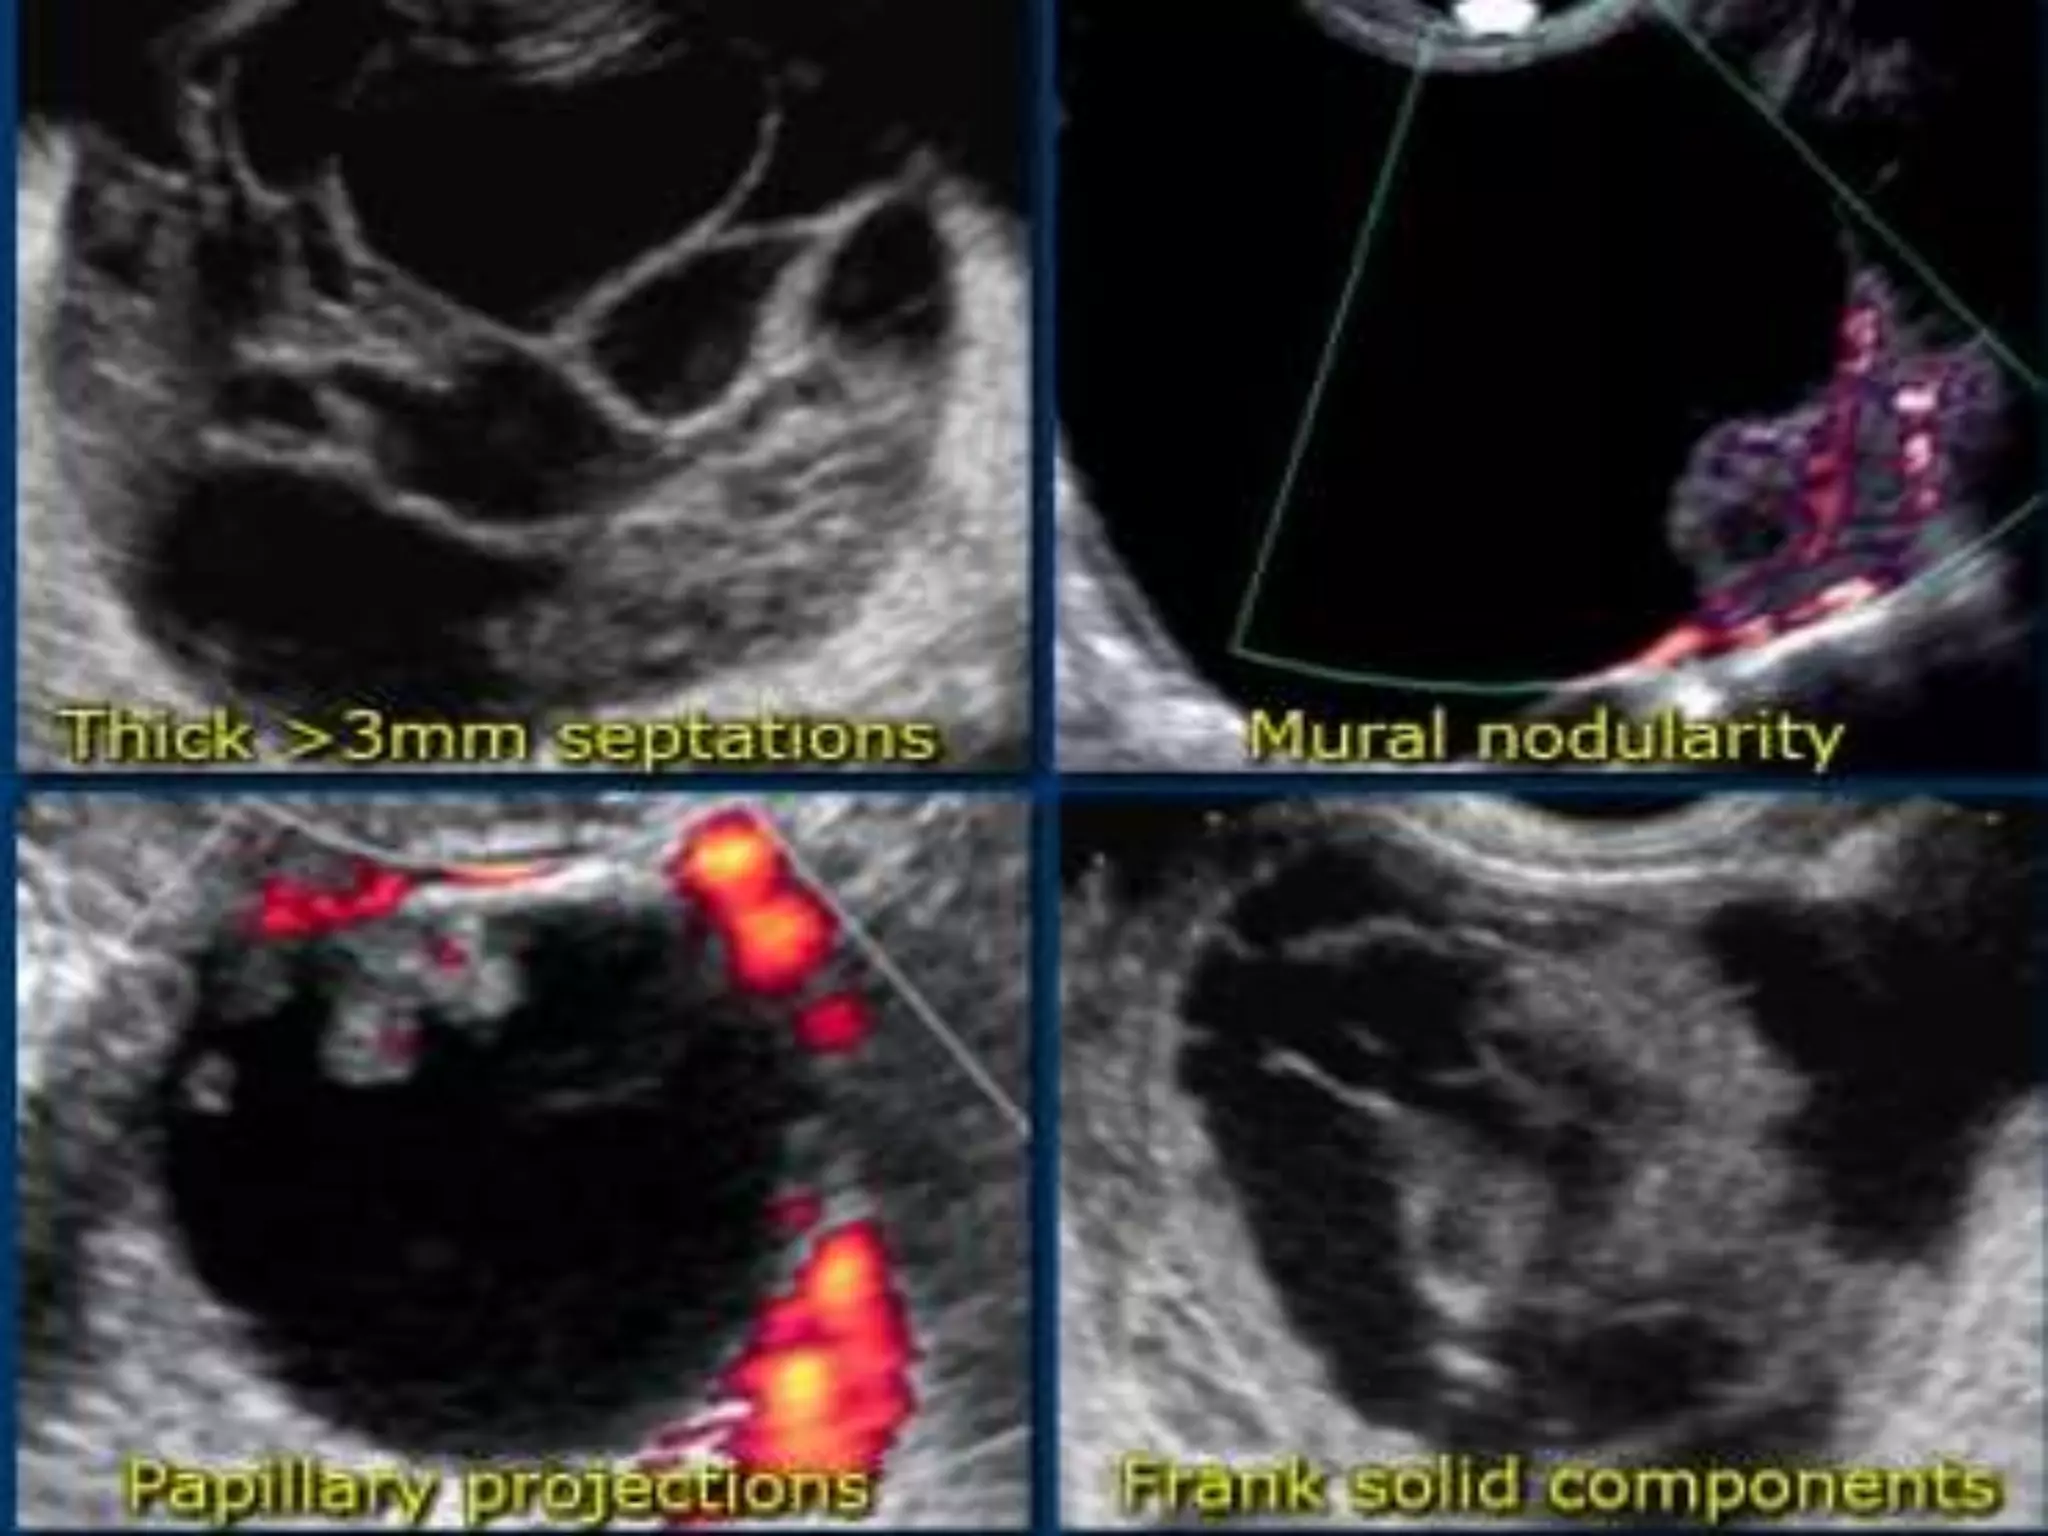

• Morphologic features at US that are suggestive of ovarian

malignancy include

– an irregular solid mass

– an irregular multilocular cystic mass

– solid components or papillary vegetations on the cyst wall

– high flow within solid components on color Doppler images

– ascites

– peritoneal nodules and other evidence of metastases.

• Solid components or papillary projections in a cystic adnexal

mass on gray-scale US images are the most significant

indicators of malignancy.

• the presence of both solid and cystic areas within a

lesion;

• necrosis within a solid lesion;

• papillary projections from the wall or septum of a

cystic lesion;

• an irregular septum or wall;

• multiple thickened (>3 mm) septations;

• a large size (>6 cm);

• bilateral lesions;

• and ascites, peritoneal disease, or lymphadenopathy